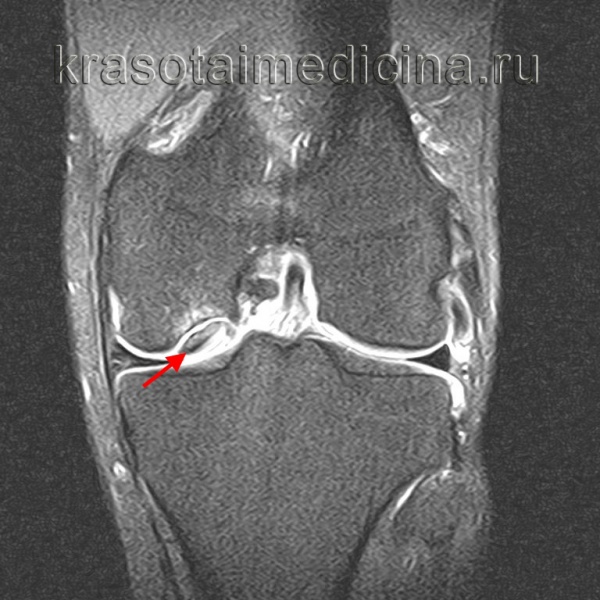

МРТ коленного сустава. Рассекающий остеохондрит медиального мыщелка бедренной кости, стадия отграничения.

9. МРТ позволяет оценить размеры очага, целостность хрящевого покрова и подлежащей субхондральной кости, охарактеризовать поражение как стабильное или нестабильное:

• МР-признаки нестабильного поражения включают: (1) полоса высокоинтенсивного сигнала по периферии очага на Т2-взвешенных изображениях (рис. 3), (2) полоса высокоинтенсивного сигнала, проходящая через суставную поверхность, на Т2-взвешенных изображениях, (3) формирование субхондральных кист и (4) дефект суставной поверхности